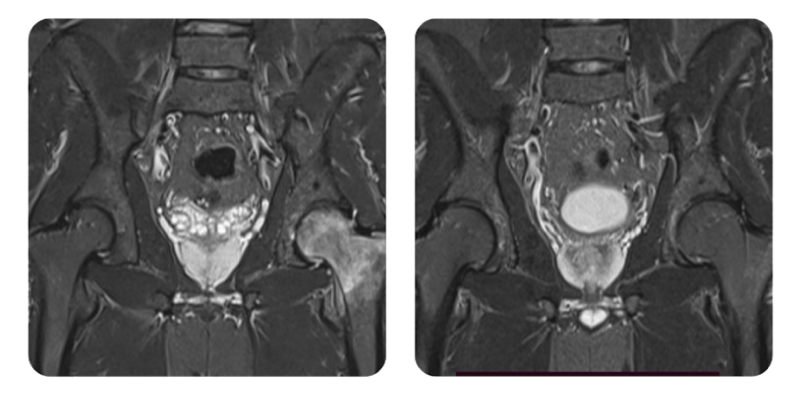

Prima

Dopo

R.M., 36 anni - Necrosi avascolare (asettica) della testa femorale, stadio 1/2

Diagnosi: Necrosi asettica della testa femorale, stadio I/II secondo Arlet e Ficat.

Evoluzione: Dopo 30 sedute di ossigenoterapia iperbarica, il paziente si presenta alla rivalutazione e riferisce di aver gia ripreso il lavoro; il dolore e diminuito da 8/10 a 3-4/10. Soggettivamente, si sente molto meglio.

Risultato: L'edema si e ridotto di circa il 60-70%, con comparsa di edema minimo a livello dell'acetabolo. In seguito a questo progresso, si raccomanda un ulteriore ciclo di 20 sedute.